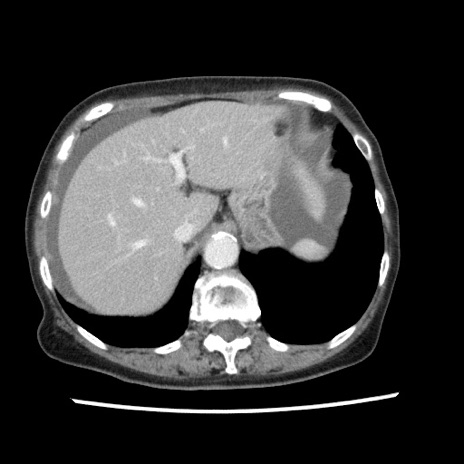

【症例】80歳代女性

【主訴】腹痛

【現病歴】8時間前から腹痛あり来院。

【既往歴】糖尿病、脂質異常症、子宮体癌にて子宮全摘術

【身体所見】意識清明・会話良好だが腹痛で苦悶様、全腹部にわたって反跳痛と圧痛あり

【データ】WBC 13600、CRP 0.14、LDH 224、CK 90